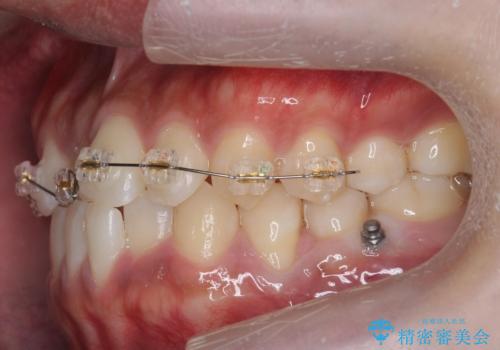

骨格性の受け口の矯正 部分ワイヤーで上の前歯を前に、 マウスピースで下の前歯を後ろに。

- インビザライン ワイヤー矯正

骨格性の受け口だったため、矯正用のミニスクリューを用いて、下の前歯をしっかり内側に入れました。

また、下顎はミニスクリューからマウスピースにゴムをかけて、下の歯並びが前に出ないようにして並べています。